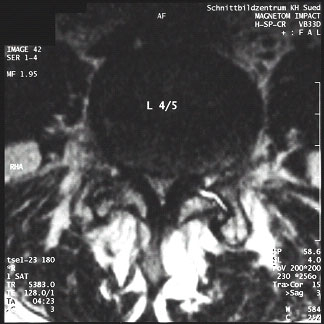

Abb:1- 3

59jährige Patientin mit einem Wirbelgleiten zwischen dem 4. und 5. Lendenwirbelkörper und einer daraus resultierenden Einengung des Wirbelkanals (Pseudospondylolisthese bei Spinalkanalstenose. Normales seitliches Röntgenbild (links), Kernspintomographien (mitte und rechts).